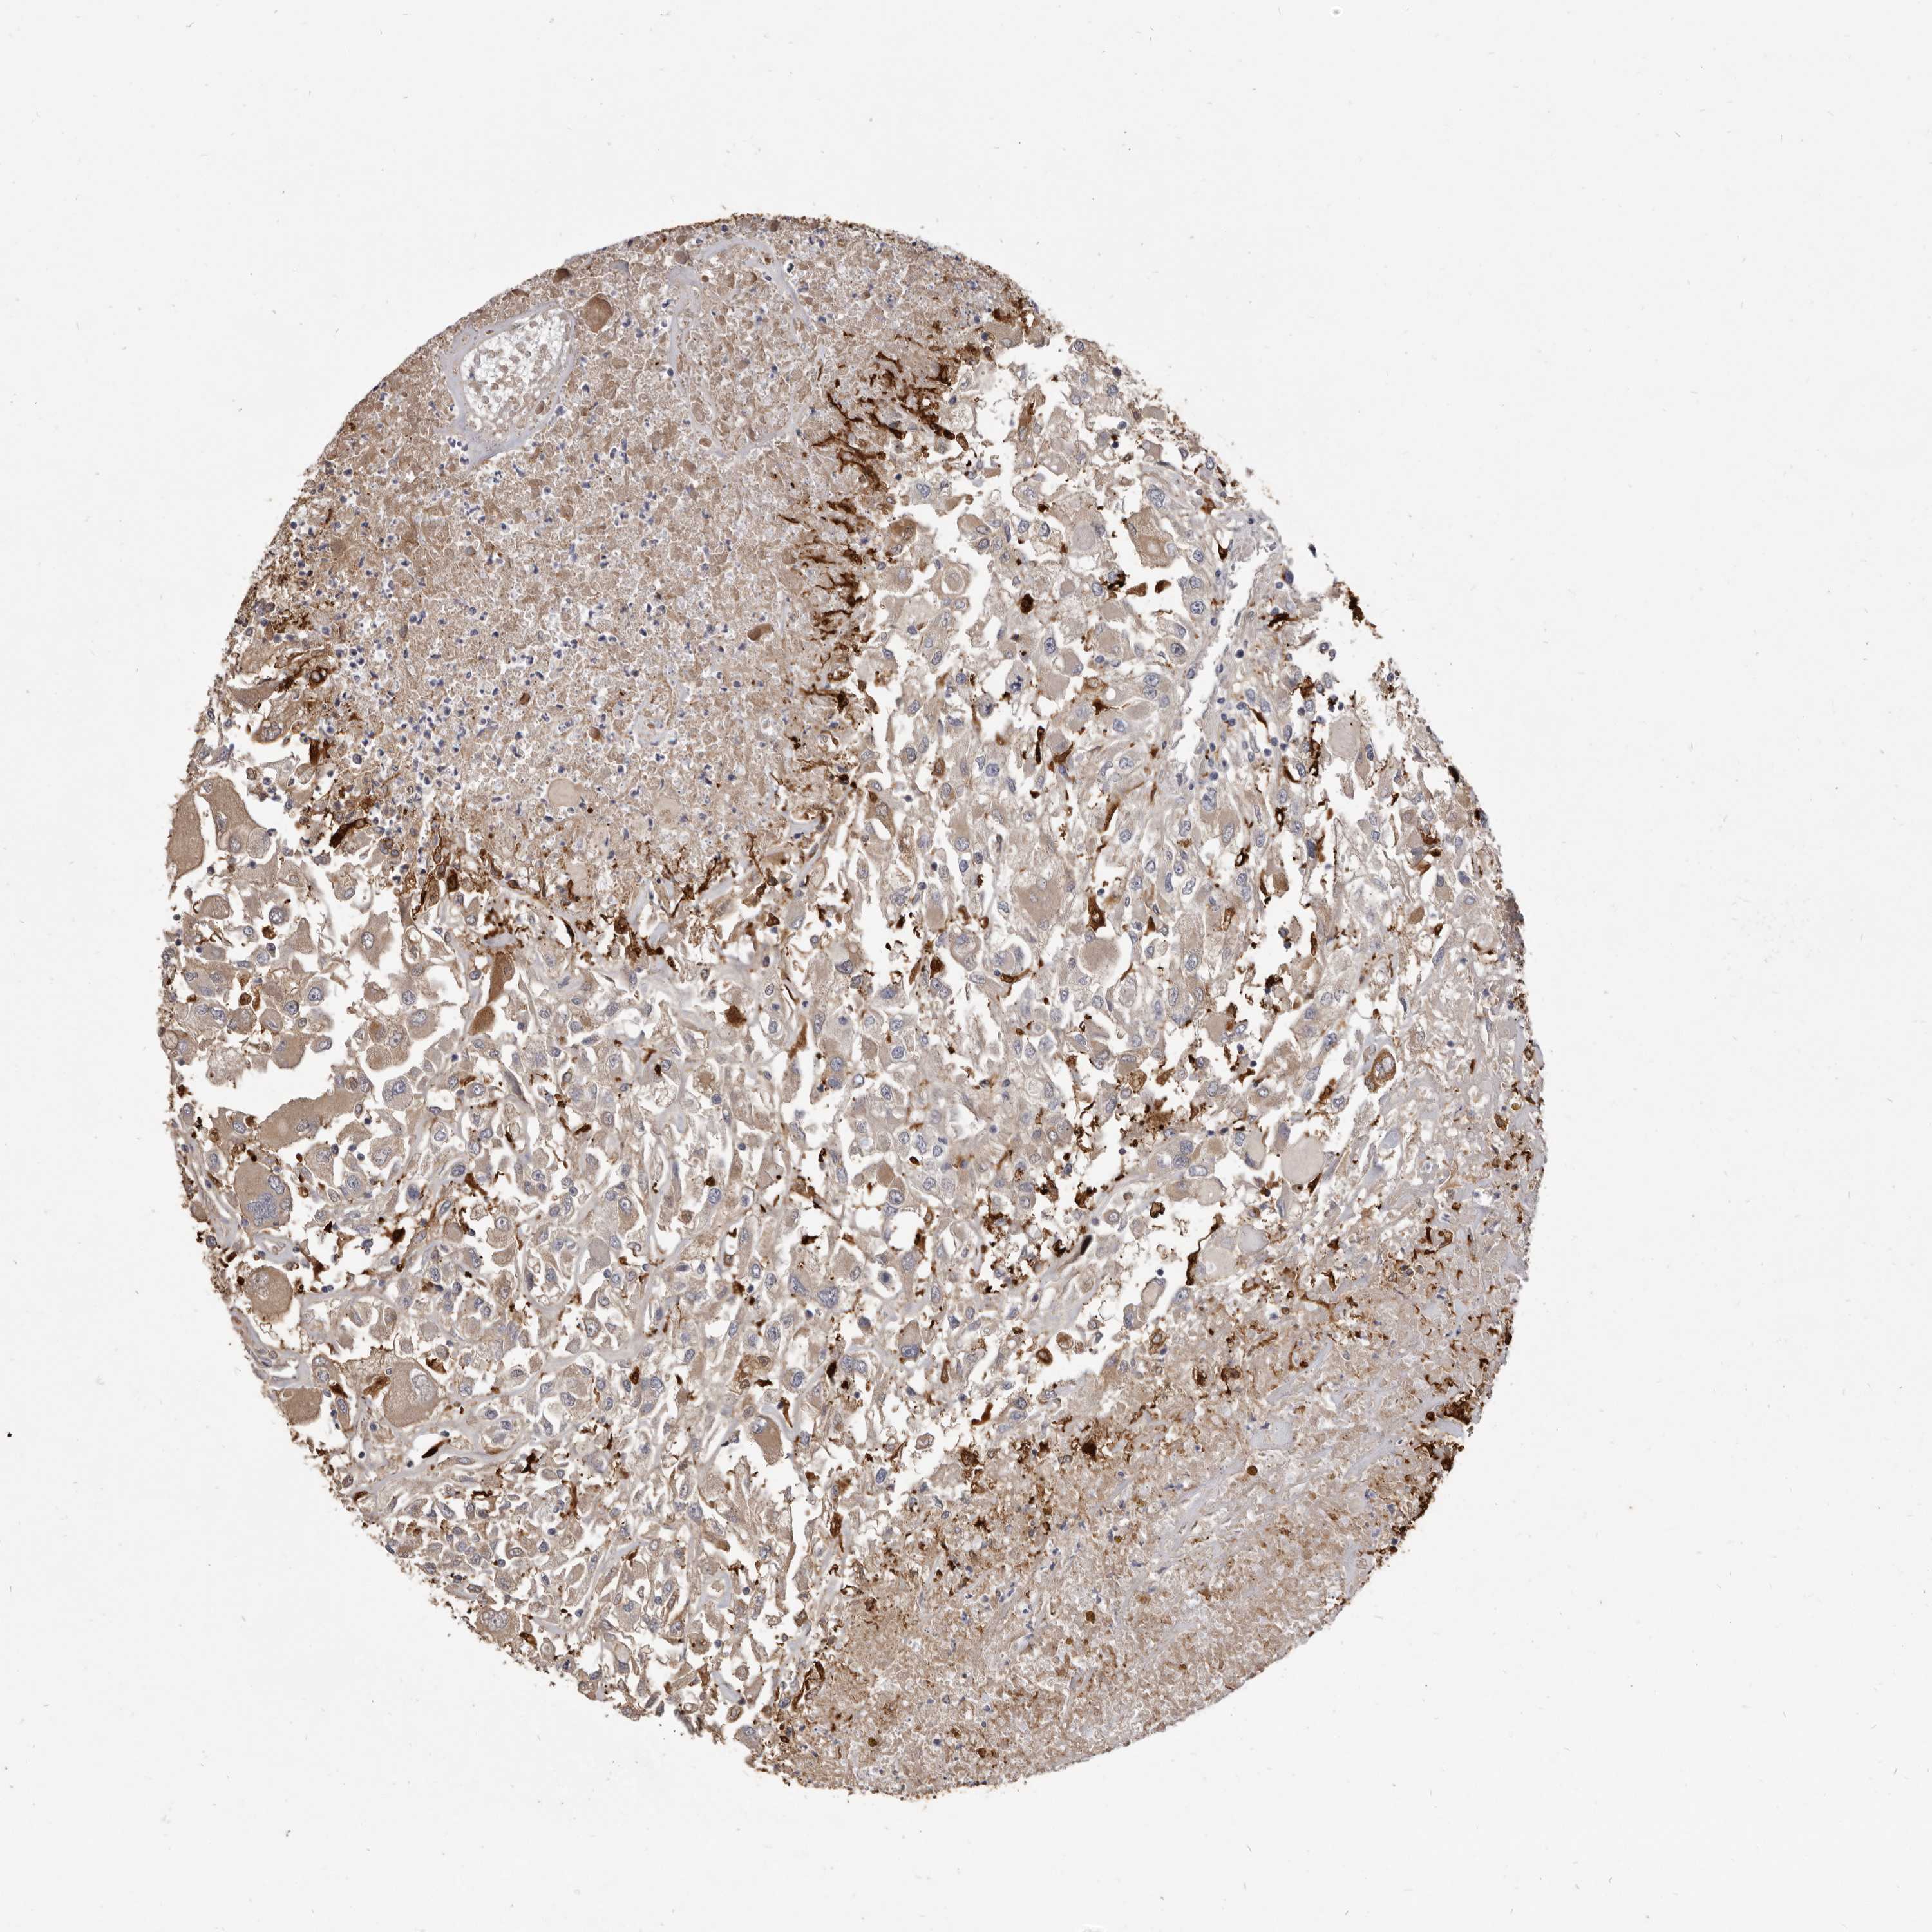

KIDNEY RENAL CLEAR CELL CARCINOMA (VALIDATION) - Interactive survival scatter ploti

The Survival Scatter plot shows the clinical status (i.e. dead or alive) for all individuals in the patient cohort, based on the same data that underlies the corresponding Kaplan-Meier plots. Patients that are alive at last time for follow-up are shown in blue and patients who have died during the study are shown in red.

The x-axis shows the expression levels (FPKM) of the investigated gene in the tumor tissue at the time of diagnosis. The y-axis shows the follow-up time after diagnosis (years). Both axes are complimented with kernel density curves demonstrating the data density over the axes. The top density plot shows the expression levels (FPKM) distribution among dead (red) and alive patients (blue). The right density plot shows the data density of the survived years of dead patients with high and low expression levels respectively, stratified using the cutoff indicated by the vertical dashed line through the Survival Scatter plot. This cutoff is automatically defined based on the FPKM cutoff that minimizes the p-score. The cutoff can be changed by dragging the vertical line or by entering a cutoff value in the square labeled "Current cut-off".

Under the Survival Scatter plot the p-score landscape (black curve; left axis) is shown together with dead median separation (red curve; right axis). Dead median separation is the difference in median mRNA expression between patients who have died with high and low expression, respectively. It is calculated as follows: median FPKM expression of dead patients with high expression - median FPKM expression of dead patients with low expression. This is intended to aid the user in visually exploring custom cutoffs and the associated p-scores and dead median separation.

Individual patient data is displayed and can be filtered by clicking on one or more of the category buttons on the top of the page. Categories describing expression level and patient information include: high, low, alive, dead, female, male and tumor stages. The scale of the x-axis can be toggled between linear and log-scale by clicking on the "x log" button. Mouse-over function shows TCGA ID, patient information and mRNA expression (FPKM) for each patient.

& Survival analysisi

Kaplan-Meier plots summarize results from analysis of correlation between mRNA expression level and patient survival. Patients were divided based on level of expression into one of the two groups "low" (under cut off) or "high" (over cut off). X-axis shows time for survival (years) and y-axis shows the probability of survival, where 1.0 corresponds to 100 percent.

VPS45 is not prognostic in Kidney Renal Clear Cell Carcinoma (validation)

Best expression cut offi

Based on the FPKM value of each gene, patients were classified into two groups and association between prognosis (survival) and gene expression (FPKM) was examined. The best expression cut-off refers the FPKM value that yields maximal difference with regard to survival between the two groups at the lowest log-rank P-value. Best expression cut-off was selected based on survival analysis .

When clicking on this number, the vertical dashed line indicating cut-off, the interactive survival plot, and the Kaplan-Meier curve will be adjusted to show results based on the best expression cut-off.

: 20.28

P scorei

Log-rank P value for Kaplan-Meier plot showing results from analysis of correlation between mRNA expression level and patient survival.

N/A

Average pTPM 19.3

Number of samples 100